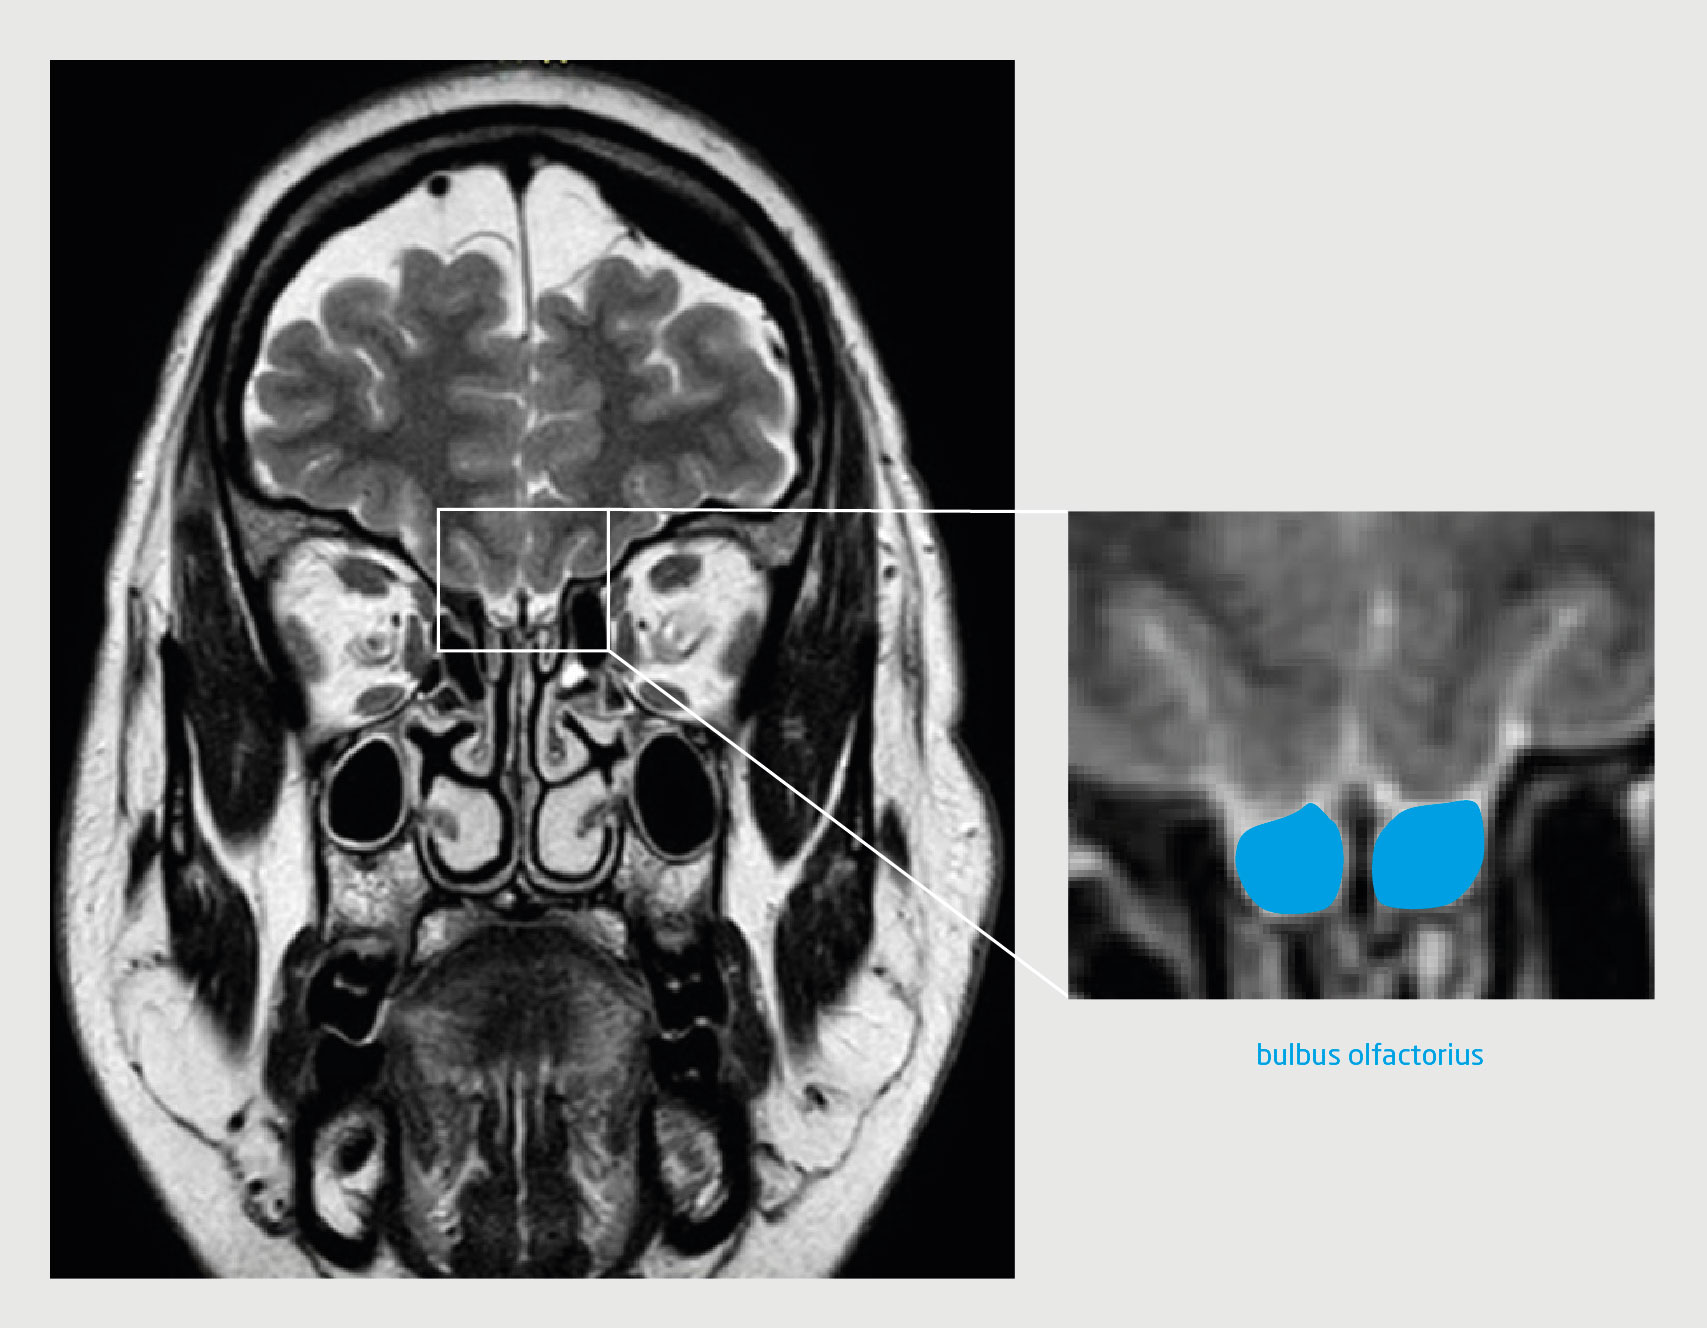

Patiënt C, een 53-jarige vrouw met idiopathische intracraniële hypertensie, bezocht de polikliniek KNO vanwege een afwezigheid van reukvermogen. Dit had zich langzaam progressief ontwikkeld. Zij had geen rinosinogene klachten en het KNO-onderzoek liet een vrije reukspleet en rustig slijmvlies zien. De score op de reuktest paste bij anosmie. Een MRI-scan liet beiderzijds een verwijd cavum van Meckel zien, een partieel ‘empty sella sign’ en een prominente hoeveelheid liquor bilateraal rondom de n. opticus en n. oculomotorius ter hoogte van de sinus cavernosus, passend bij intracraniële hypertensie. De n. olfactorius had beiderzijds een hypoplastisch aspect, waarschijnlijk door compressie bij chronisch verhoogde druk (figuur 2).

Figuur 2 | De hersenen van de patiënte met intracraniële hypertensie

T2-gewogen turbospinecho-MRI van de hersenen van patiënt C (coronale coupe). Op deze scan van de voorste schedelbasis ter hoogte van de fossa olfactorius is bilateraal een hypoplastische, concave bulbus olfactorius te zien.